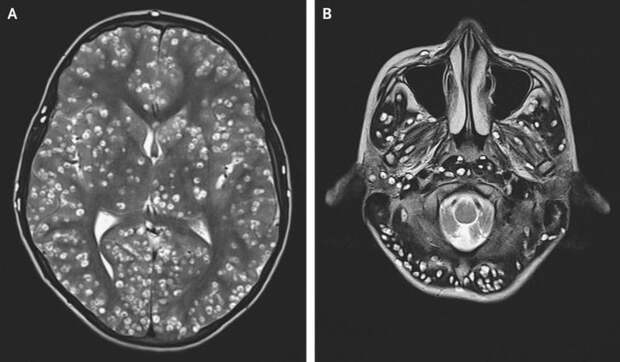

Когда в одну из индийских клиник обратился 18-летний парень с жалобами на сильную головную боль и судороги, врачи не сразу смогли понять причину его столь тяжкого состояния. Но вскоре результаты сканирования МРТ выявили нечто жуткое: мозг молодого человека был пронизан огромными кистами!

Состояние пациента характеризуется как нейроцистицеркоз, который вызывают паразитические ленточные черви — свиной цепень Taenia solium. Каждая киста на самом деле представляет собой капсулу, внутри которой развивается личинка паразита. Дальнейшее обследование показало, что кора головного мозга, мозжечок и даже стволовая часть мозга были усеяны этими так называемыми цистицерками. Кроме того, УЗИ выявило наличие личинок в правом яичке и правом глазу пациента.Когда паразит откладывает яйца, они разносятся с током крови по всему организму и прикрепляются к мышечной ткани. Жертва может годами не испытывать никаких симптомов, пока в один прекрасный день обитатели его организма не разовьются настолько, что вызовут сильную воспалительную реакцию. Из-за обилия паразитов врачи даже не смогли назначить обычные противогельминтные препараты — это могло спровоцировать такое сильное воспаление, которое могло убить пациента.